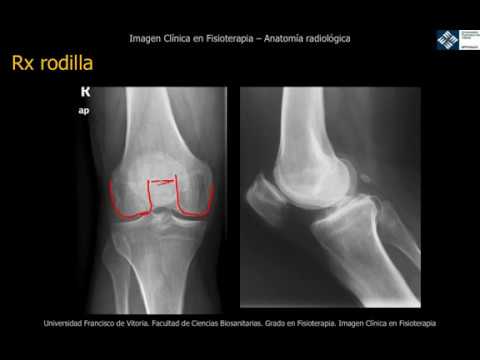

Radiografía anteroposterior (AP)

La radiografía anteroposterior es uno de los tipos más comunes de radiografía de rodilla y se realiza con el paciente de pie o sentado. Se toman dos imágenes de cada rodilla, una desde el frente (vista anteroposterior) y otra desde el costado (vista lateral). Esta radiografía proporciona información detallada sobre la alineación de los huesos de la rodilla, así como sobre el espacio articular y posibles desgastes.

Radiografía lateral

La radiografía lateral se realiza con el paciente de pie o sentado, y se toma una imagen desde el costado de la rodilla. Esta radiografía proporciona una vista detallada de la articulación de la rodilla en posición lateral. Es especialmente útil para evaluar lesiones en los ligamentos y la cápsula articular, así como patologías como la condromalacia rotuliana.